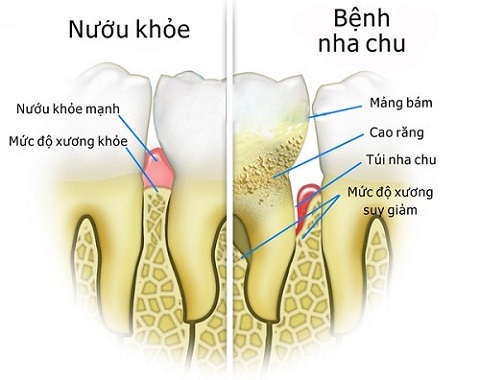

I. Nha chu và bệnh nha chu là gì?

Nha chu là tổ chức các mô xung quanh chân răng có chắc năng bảo vệ và nâng đỡ chân răng, giúp răng khỏe mạnh.

II. Bệnh nha chu là gì và tác hại của nó?

Bệnh nha chu là hiện tượng viêm nhiễm các vùng mô xung quanh chân răng. Khi nướu và các mô xung quanh chân răng bị viêm nhiễm, chúng sẽ tách ra khỏi chân răng, chân răng không còn lớp nâng đỡ và bảo vệ, ở xương chân răng cũng bị viêm nhiễm dẫn đến tiêu xương hàm. Cuối cùng là lung lay chân răng và mất răng nếu không điều trị kịp thời.